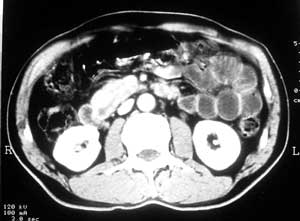

十二指肠炎

患者,男,57岁,梗阻性黄疸10余天。

这个病例胰头无明显增大,胆总管扩张明显而肝内胆管扩张更不明显,病程较短,

注意到十二指肠乳头明显突出,但尚光滑。分析以下可能性:

1、十二指肠乳头本身的病变,如乳头炎症;

2、急性乳头水肿,胆总管下端结石排石后乳头水肿;

3、壶腹部胆总管下端肿瘤累及十二指肠乳头。

病理结果

十二指肠乳头粘膜慢性非特异性炎症